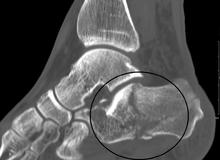

Conventional radiography is usually the initial assessment tool when calcaneal fracture is suspected. Recommended x-ray views are (a) axial, (b) anteroposterior, (c) oblique views and (d) views with dorsiflexion and internal rotation of the foot. However, conventional radiography is limited for visualization of calcaneal anatomy, especially at the subtalar joint. CT Scan is currently the imaging study of choice for evaluating calcaneal injury and has substituted conventional radiography in the classification of calcaneal fractures.[11] Axial and coronal views are taken for proper visualization of the calcaneus, subtalar, calcaneocuboid and talonavicular joints.